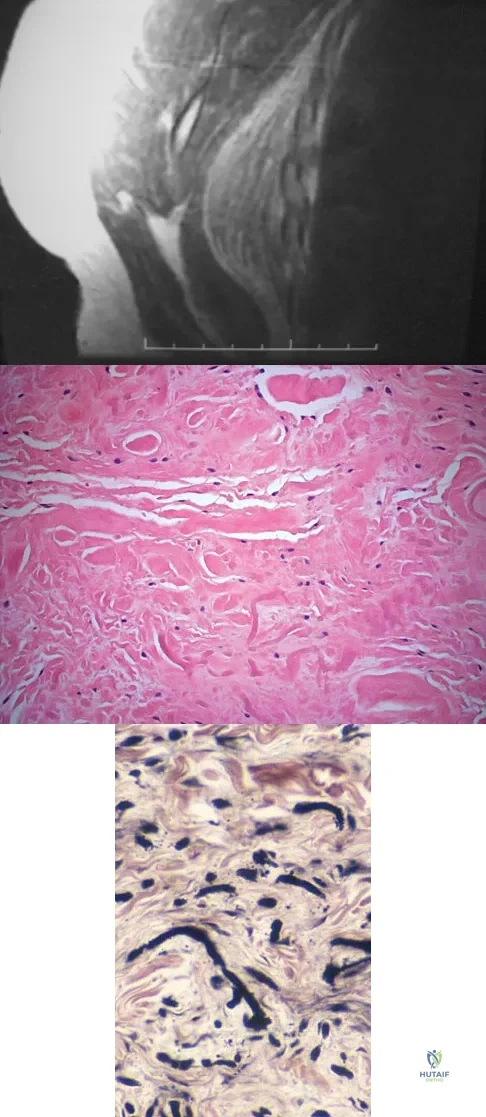

A 17-year-old boy has had elbow pain for the past 6 weeks. A radiograph, MRI scans, and biopsy specimens are shown in Figures 65a through 65e. What is the most likely diagnosis?

Which of the following prognostic indicators is associated with the least favorable outcome for patients newly diagnosed with osteosarcoma?